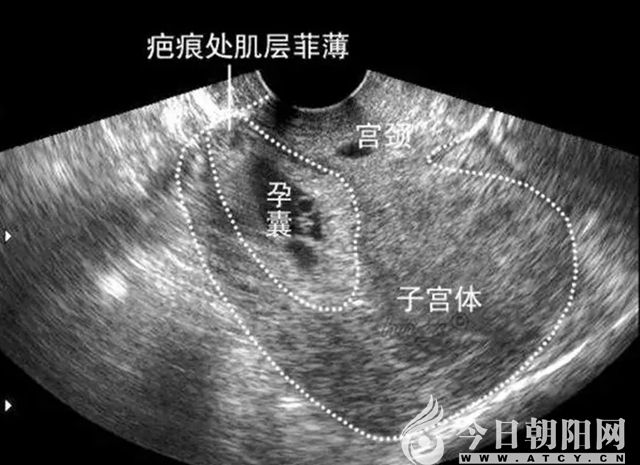

近年來,腔鏡手術(shù)以其創(chuàng)傷小、出血少、病人痛苦少、術(shù)后恢復(fù)快等優(yōu)勢,正逐步替代大部分傳統(tǒng)手術(shù)。在這方面,該院婦科走在了省內(nèi)同級醫(yī)院的前列。目前,已開展的腹腔鏡手術(shù)有:腹腔鏡下輸卵管切除術(shù)、輸卵管整形術(shù)、卵巢腫瘤剝除術(shù)、子宮肌瘤核除術(shù)、全子宮切除術(shù)及盆腔淋巴結(jié)清掃術(shù)等;開展的宮腔鏡技術(shù)有:宮腔鏡檢查術(shù)、宮腔鏡下子宮內(nèi)膜息肉切除術(shù)、子宮粘膜下肌瘤電切術(shù)、異位節(jié)育環(huán)取出術(shù)、子宮縱膈切除術(shù)、剖宮產(chǎn)癍痕妊娠修補(bǔ)術(shù)等。